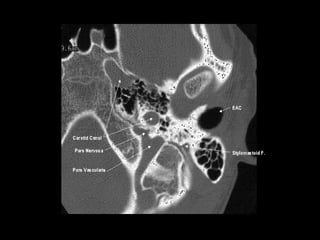

Radiographers use medical imaging equipment like X-rays and MRIs to produce images of patients' internal structures and organs. They are responsible for positioning patients, operating scanning machines, and ensuring quality images. Radiographers must have strong attention to detail, excellent communication skills, and the ability to work well under pressure to accurately capture anatomical features and diagnose any abnormalities.